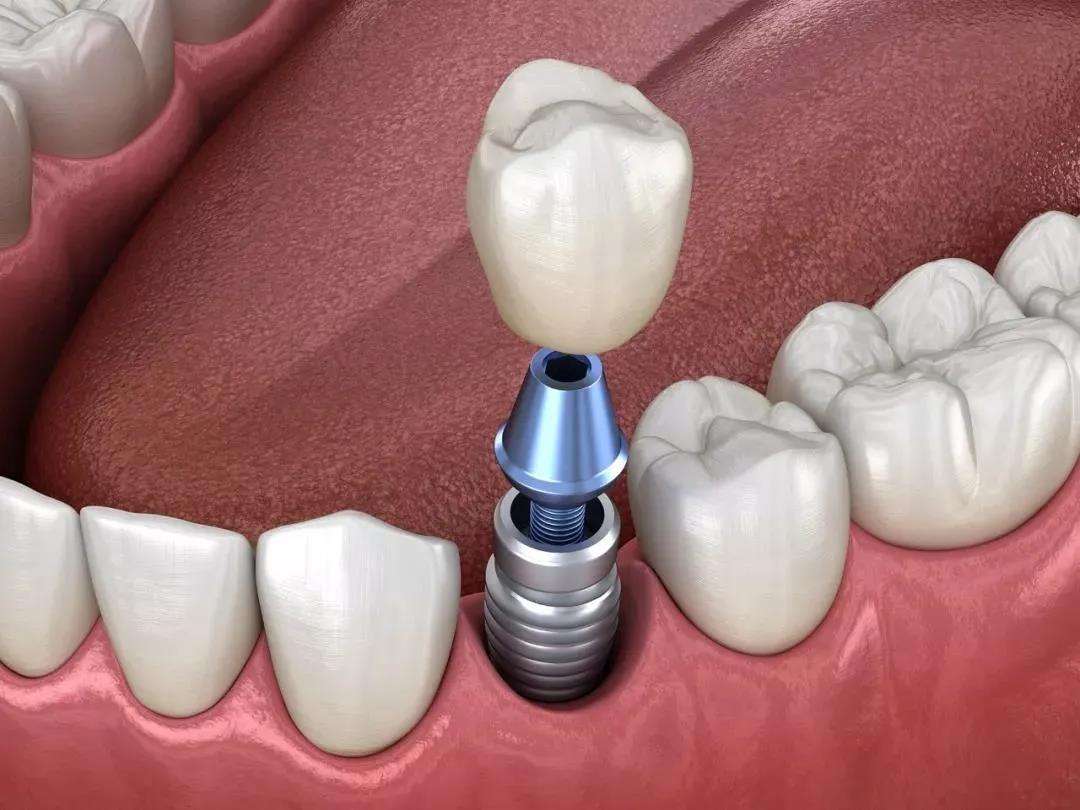

牙齿缺失,对咀嚼消化、外貌颜值等诸多方面都造成了不好的影响。关于牙齿缺失,我们知道常见的修复方式有:固定(或活动)义齿和人工种植牙,但大部分市民都会觉得种牙贵。

二、自体牙移植的优势是什么?把自身“闲置”的牙齿移植到空缺的牙槽窝内,不仅“变废为宝”,还打破了种植牙“一统江湖”的地位,价格上更是“接地气儿”;

而相较于活动和固定假牙,自体牙移植在功能、调节时间和与生物相容性等方面都具有较高的优越性,而且可以和其他正常牙齿一样正常发挥作用。